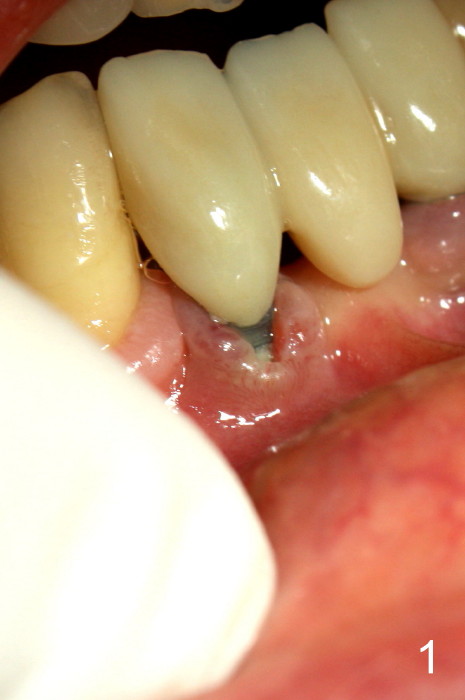

The patient has had chronic pain and swelling associated with the implant at the site of #26 (Fig.1). The extent of implant thread exposure is shown in Fig.2 after flap reflection; inflammatory granulation tissue is present around the most coronal threads (*, one year post cementation). Following debridement and Clindamycin soaking, allograft is placed around the exposed threads; a titanium mesh is used to contain the graft (Fig.3). The flap is closed with tension in spite of the periosteum being underscored. The patient develops moderate to severe ecchymosis postop.

Fig.5 is taken following local anesthesia to show the exposed mesh, 22 days post placement. When the latter is removed, the exposed threads appear to be less (Fig.6, as compared to Fig.2). There is healthy granulation tissue growth apically (*). The patient is asymptomatic 1 month post mesh removal; there is no tenderness around exposed threads (Fig.7). Connective tissue graft is planned to cover the exposed threads through tunnel technique. Thread exposure appears less 3 months post mesh removal (Fig.8). There is infection when the region is not kept clean (Fig.9 (2.5 years post mesh removal)). The other 1-piece implant should have minor implant exposure (<). It appears that there is no thread exposure associated with the immediate implant at #28. Using smaller 1-piece implants (2.5 or 2.0 vs. 3 mm) with flap surgery should be able to prevent the complication. The 72-year-old phobic patient declines any further treatment. Two years later, she agrees to have treatment because of repeated infection (Fig.10). Impression has been taken for stent. After sectioning FPD and removing the infected implant (Tatum), a smaller implant will be placed in between the implants. If her vein is not too small, blood will be drawn for PRF.